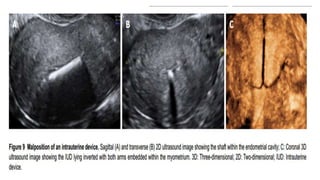

IUCD

– Location of intrauterine

contraceptive devices:

displacement of intrauterine

contraceptive devices can

reduce their effectiveness.

The coronal plane images

provided by 3D ultrasound

provide views of both the

arms and shaft of the device

and the relation of these to

the endometrial cavity.